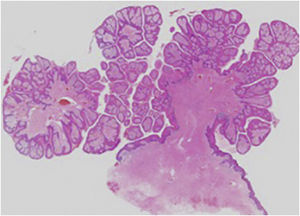

Um homem de 83 anos procurou cuidados médicos com queixa de múltiplos nódulos na bolsa escrotal, que apareceram pela primeira vez 20 anos antes. Eles estavam aumentando de tamanho e recentemente começaram a sangrar facilmente. O exame físico revelou dois nódulos vermelhos exofíticos e pedunculados, medindo 25×25mm e 13×13mm, que se projetavam de ambos os lados da bolsa escrotal (fig. 1). O paciente tinha história de câncer de próstata, cardiomiopatia hipertrófica obstrutiva, insuficiência aórtica, fibrilação atrial crônica, insuficiência renal crônica e tumores submucosos no esôfago. A histopatologia das lesões mostrou tumores exofíticos com acantose e papilomatose (fig. 2). As papilas dérmicas estavam ocupadas por numerosos histiócitos espumosos e hiperplasia de capilares (fig. 3). As células espumosas coraram‐se pelo ácido periódico de Schiff (PAS) e foram imunorreativas com o antígeno CD68 (fig. 4).

Considerando os achados histopatológicos, os nódulos foram diagnosticados como xantoma verruciforme (XV). Xantogranuloma foi excluído porque não foram observadas células gigantes do tipo Touton. Ambos os nódulos foram removidos cirurgicamente e mostraram as mesmas características histopatológicas. Nenhuma recorrência foi observada durante o seguimento de um ano.

O XV ocorre principalmente na cavidade oral;1 entretanto, a área genital também é afetada (XV associado à área genital).2 Clinicamente, os XVs têm aparência semelhante ao condiloma acuminado ou à verruga vulgar. O exame histopatológico demonstra hiperplasia verrucosa da epiderme e número variável de células espumosas nas papilas dérmicas. Que seja de conhecimento dos autores, apenas seis casos de múltiplos XVs na área genital foram relatados, incluindo o presente caso (tabela 1).3–7 Esses seis casos consistiram em quatro pacientes do sexo masculino e duas do sexo feminino, com média de idade de 53 anos (variando de 29 a 83 anos). O tamanho das lesões variou de 3 a 25mm. O presente caso apresentava dois nódulos, enquanto numerosos nódulos foram observados em um caso.3 Prurido foi observado em dois casos, enquanto outros eram assintomáticos. Um caso de XV ocorreu no local de enxerto de pele em virtude de fasciíte necrosante.5